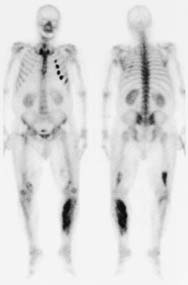

- Age/Sex: 66M

- Chief Complaint:椉壓巿捝偍傛傃峠挭

- 偁傞昦堾偵擖堾拞偺姵幰偵婲偙偭偨偱偒偛偲偱偡(偙偺強尒偑尨場偱擖堾偵側偭偨傢偗偱偼偁傝傑偣傫乯丅

- 側偤偙傫側強尒偵側偭偨偺偐丠峫偊偰梸偟偄偲偺弌戣幰偐傜偺僐儊儞僩偱偡丅

- Images:

- Bone scan

|

Whole-body

magnify magnify

|

Left lateral view

|

偁側偨偺恌抐偼 What

is your first impression?